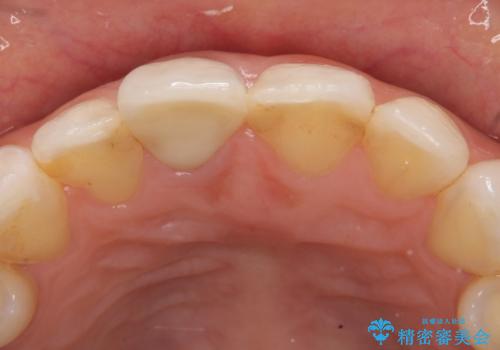

- 右上1番目の歯の変色が気になると来院された方の症例です。

検査の結果、右上1の歯は失活(歯の神経が死んでいること)していたため根管治療を行いました。

その後オールセラミッククラウン(スペシャル)による補綴を行いました。

なお隣在歯の樹脂は今後治療していく予定です。